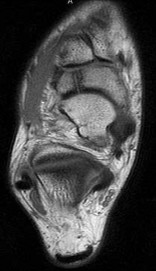

Question 4:

A 55-year-old woman feels a 'pop' in the back of her knee while squatting. An MRI is shown: A posterior horn medial meniscus root tear is identified. Biomechanically, a complete medial meniscus posterior root tear alters contact pressures to a degree equivalent to which of the following?

Correct Answer: Total meniscectomy

Explanation:

A complete posterior root tear of the medial meniscus leads to a complete loss of hoop stresses, resulting in meniscal extrusion. Biomechanically, this alters peak tibiofemoral contact pressures and reduces contact area to a degree equivalent to a total meniscectomy, leading to rapid articular cartilage degeneration.